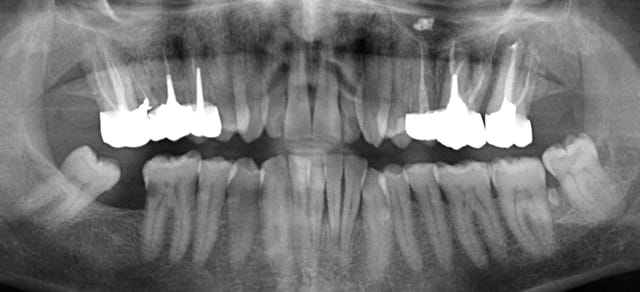

L'été dernier, en vacances chez mes parents, j'observe un abcès en palatin de la 16 de mon papa.

J'exerce à 500 km de chez lui. Je lui fais donc juste une ordonnance et un courrier précisant que j'ai observé un abcès sur la 16.

Il consulte quelques jours après. Le praticien lui dit que l'abcès est "lié au tassement alimentaire entre les 2 dernières dents" et que "pour rétablir un bon contact", il faut "couronner la dernière dent et donc la dévitaliser".

Je n'ai pas de radio pré-op de la 17 mais à l'examen visuel, il n'y avait rien ormis un amalgame peu étendu.

Quelques mois plus tard, je fais cette radiographie panoramique (ci-dessous) dans mon cabinet.

Ce praticien a dévitalisé et couronné une 17 à côté d'une 16 fracturée dont du pus suinte par le collet.

De plus, il a certifié à mon papa que "Non, il n'y a pas d'autres problèmes dans votre bouche".

Alors qu'il y a la 26 dans le même état que la 16, la 22 cariée, la 46, la parodontite des incisives mandibulaires...

A distance, je lui ai demandé de consulter un autre praticien : il ne lui propose aucune prise en charge globale. Alors je lui dis d'en voir un autre. Puis un autre.

Ce n'est que le 4ème confrère qui lui a fait un vrai bilan et un vraie prise en charge globale. Il termine le traitement mardi prochain. J'ai envie de lui envoyer quelque chose pour le remercier.